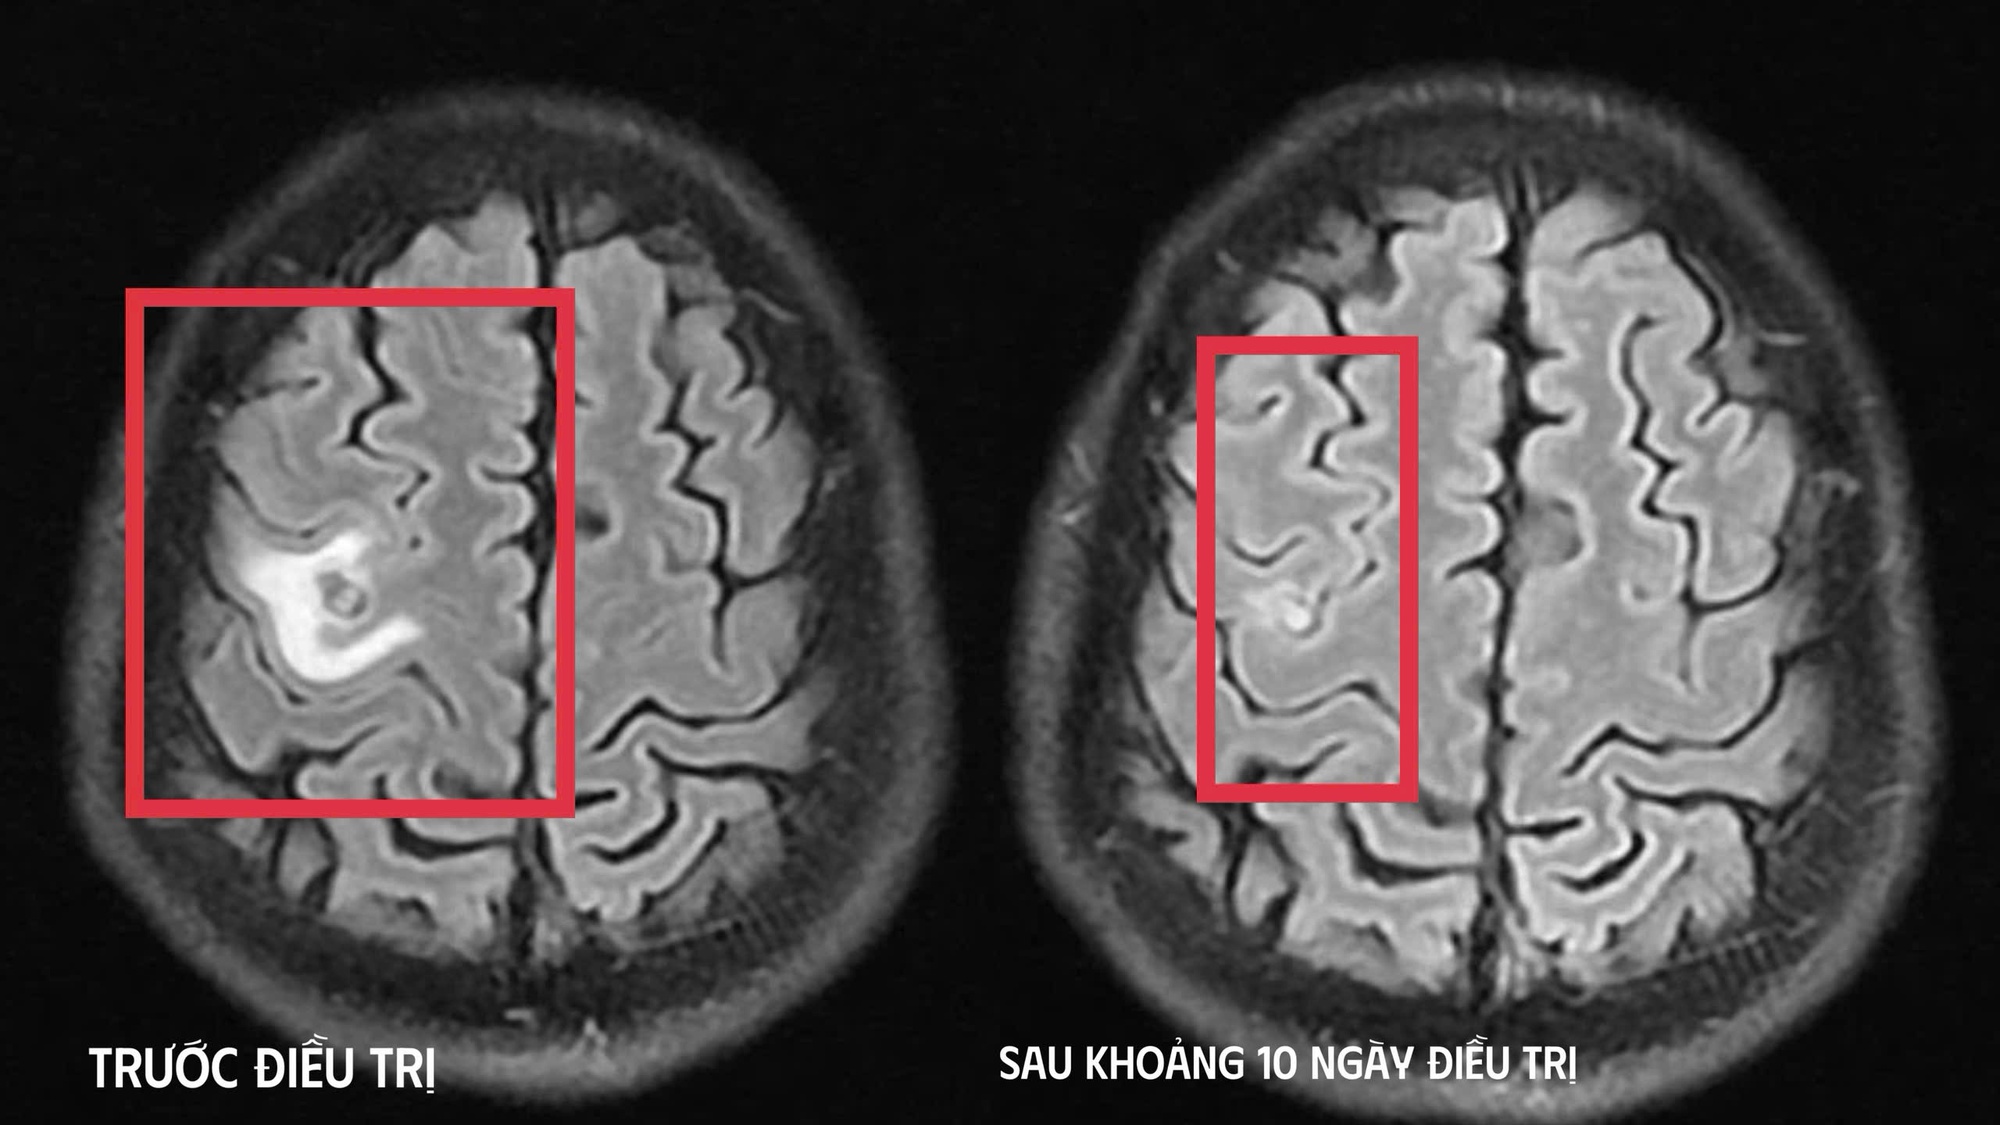

Hình ảnh chụp chiếu trước và sau khi điều trị (Ảnh: BVCC).

Kết quả chụp cộng hưởng từ (MRI) sọ não cho thấy một tổn thương dạng nang nhỏ tại thùy trán trái, kích thước khoảng 11 x 7 mm, xung quanh có phù não nhẹ. Hình ảnh này gợi ý nhiều đến tổn thương do ký sinh trùng hơn là u não nguyên phát.

Khi tái khám gần một tháng sau, phim MRI cho thấy tổn thương não thu nhỏ rõ rệt, phù não giảm, không còn dấu hiệu tiến triển, chứng tỏ đáp ứng điều trị tốt. Bệnh nhân được chỉ định thêm một đợt thuốc củng cố và theo dõi lâu dài.